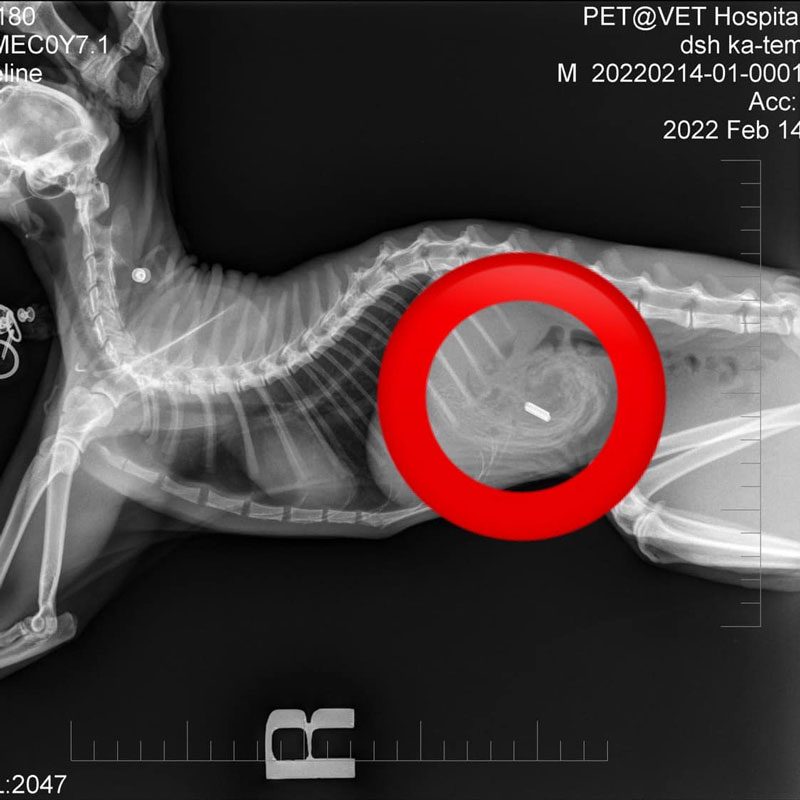

อุทาหรณ์คนเลี้ยงสัตว์… เพจเฟซบุ๊ก Kwanjai The Sphynx ขวัญใจ เดอะ สฟิงซ์ ได้โพสต์ภาพยางรัดผมที่ถูกผ่าออกมาจากท้องแมว

โดยระบุข้อความว่า “อุทาหรณ์ แมวกินยางรัดผม เคสนี้เจ้าของน้องสังเกตเห็นว่าน้องผอมลงมาก พยายามอ้วกแต่ไม่มีอะไรออกมา บางทีก็มีเลือดออก ไม่อึ พาไปตรวจเลือดก็ปกติดี จึงพาไปเอกซเรย์ เจอสิ่งแปลกปลอม ผ่าตัดออกมาเป็นยางรัดผมก้อนใหญ่มากกกก (เทียบกับเหรียญสิบข้าง ๆ)

น้องโชคดีที่ได้รับการผ่าตัดทันเวลา ก่อนที่ลำไส้จะพันกันแล้วอันตรายถึงชีวิต ตอนนี้เจ้าตัวแสบปลอดภัยแล้ว ทางเจ้าของน้องแมวฝากมาเตือน เก็บของเล็ก ๆ ในบ้านให้ดี โดยเฉพาะพวกยางเส้นๆ เข็ม เศษผ้า เศษพลาสติก เพื่อป้องกันไม่ให้เผลอกินเข้าไป หมั่นสังเกตอาการสัตว์เลี้ยงเราด้วยว่ามีอะไรผิดปกติไปจากเดิมมั้ย กินข้าวได้แค่ไหน อึเป็นยังไงบ้าง ก่อนจะสายเกินไป”. -008